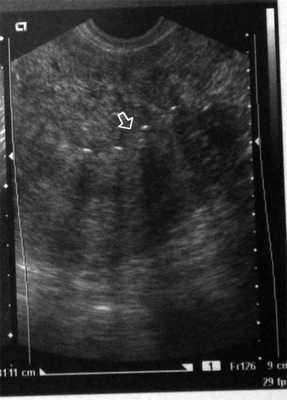

Контроль над состоянием послеоперационного рубца проводили на 7-е сутки и через 1, 3 и 6 мес после операции (см. рисунок). Рисунок 1. Ультразвуковая картина матки через 7 дней после миомэктомии с использованием нити V-lock (стрелкой указана зона шва). Ни в одном случае не отмечали формирования гематом в области швов на матке в раннем послеоперационном периоде как при наложении отдельных Z-образных швов (n=287), так и при использовании непрерывного шва нитью V-lock (n=83). Ультразвуковые критерии несостоятельности рубца к 6-му месяцу после операции не выявлены ни у одной из пациенток.